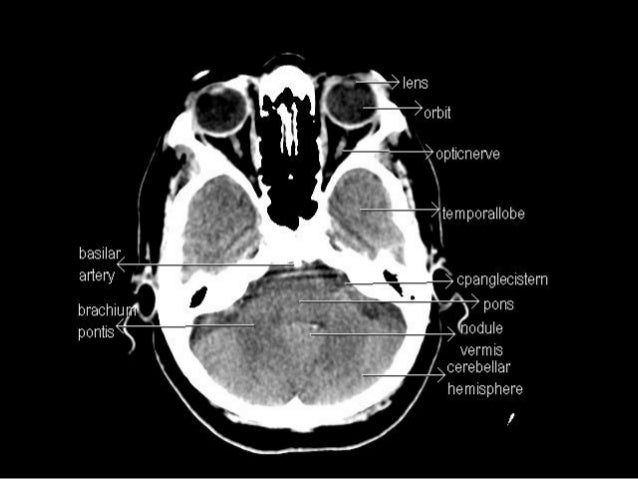

Sectional anatomy of the structures of the brain as viewed with ct mri and pet fusion imaging. It is superior to the upper pole of the right kidney whereas the left adrenal gland is anteromedial to the upper pole of the left kidney.

These labeling exercises are to aid the viewer in learning the sectional anatomy of the brain.

Learn cross sectional anatomy brain with free interactive flashcards. What is the term for the space that exists during fetal development and that disappears in most children during infancy. This video is from our cross sectional anatomy series.

Mri of the brain. Anatomy of the encephalon mri in axial slices we created a brain atlas that is an interactive tool for studying the conventional anatomy of the normal brain based on a magnetic resonance imaging exam of the axial brain. Use the mouse scroll wheel to move the images up and down alternatively use the tiny arrows on both side of the image to move the images on both side of the image to move the images.